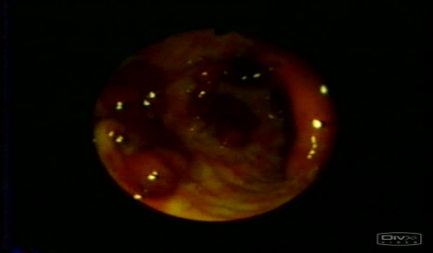

Xoralı kolitdə mukozal zədələnmənin xarakteristikası?

1.Granulyar, yastı mukoza

2. Xoralar

3.Kript absesləri

4.Mukozal damarların genişlənməsi

5.Psevdopoliplər

|

Xoralı kolitin diaqnozu üçün hansı müayinələr vacibdir?

Kolonoskopiya, biopsiya, nəcis analizi

Hansı xəstəlikdə kolonoskopik müayinədə psevdopoliplər olur?

Xoralı kolitlərdə: psevdopoliplər mukozal atrofiya fonundakı hipertrofik mukozadır.